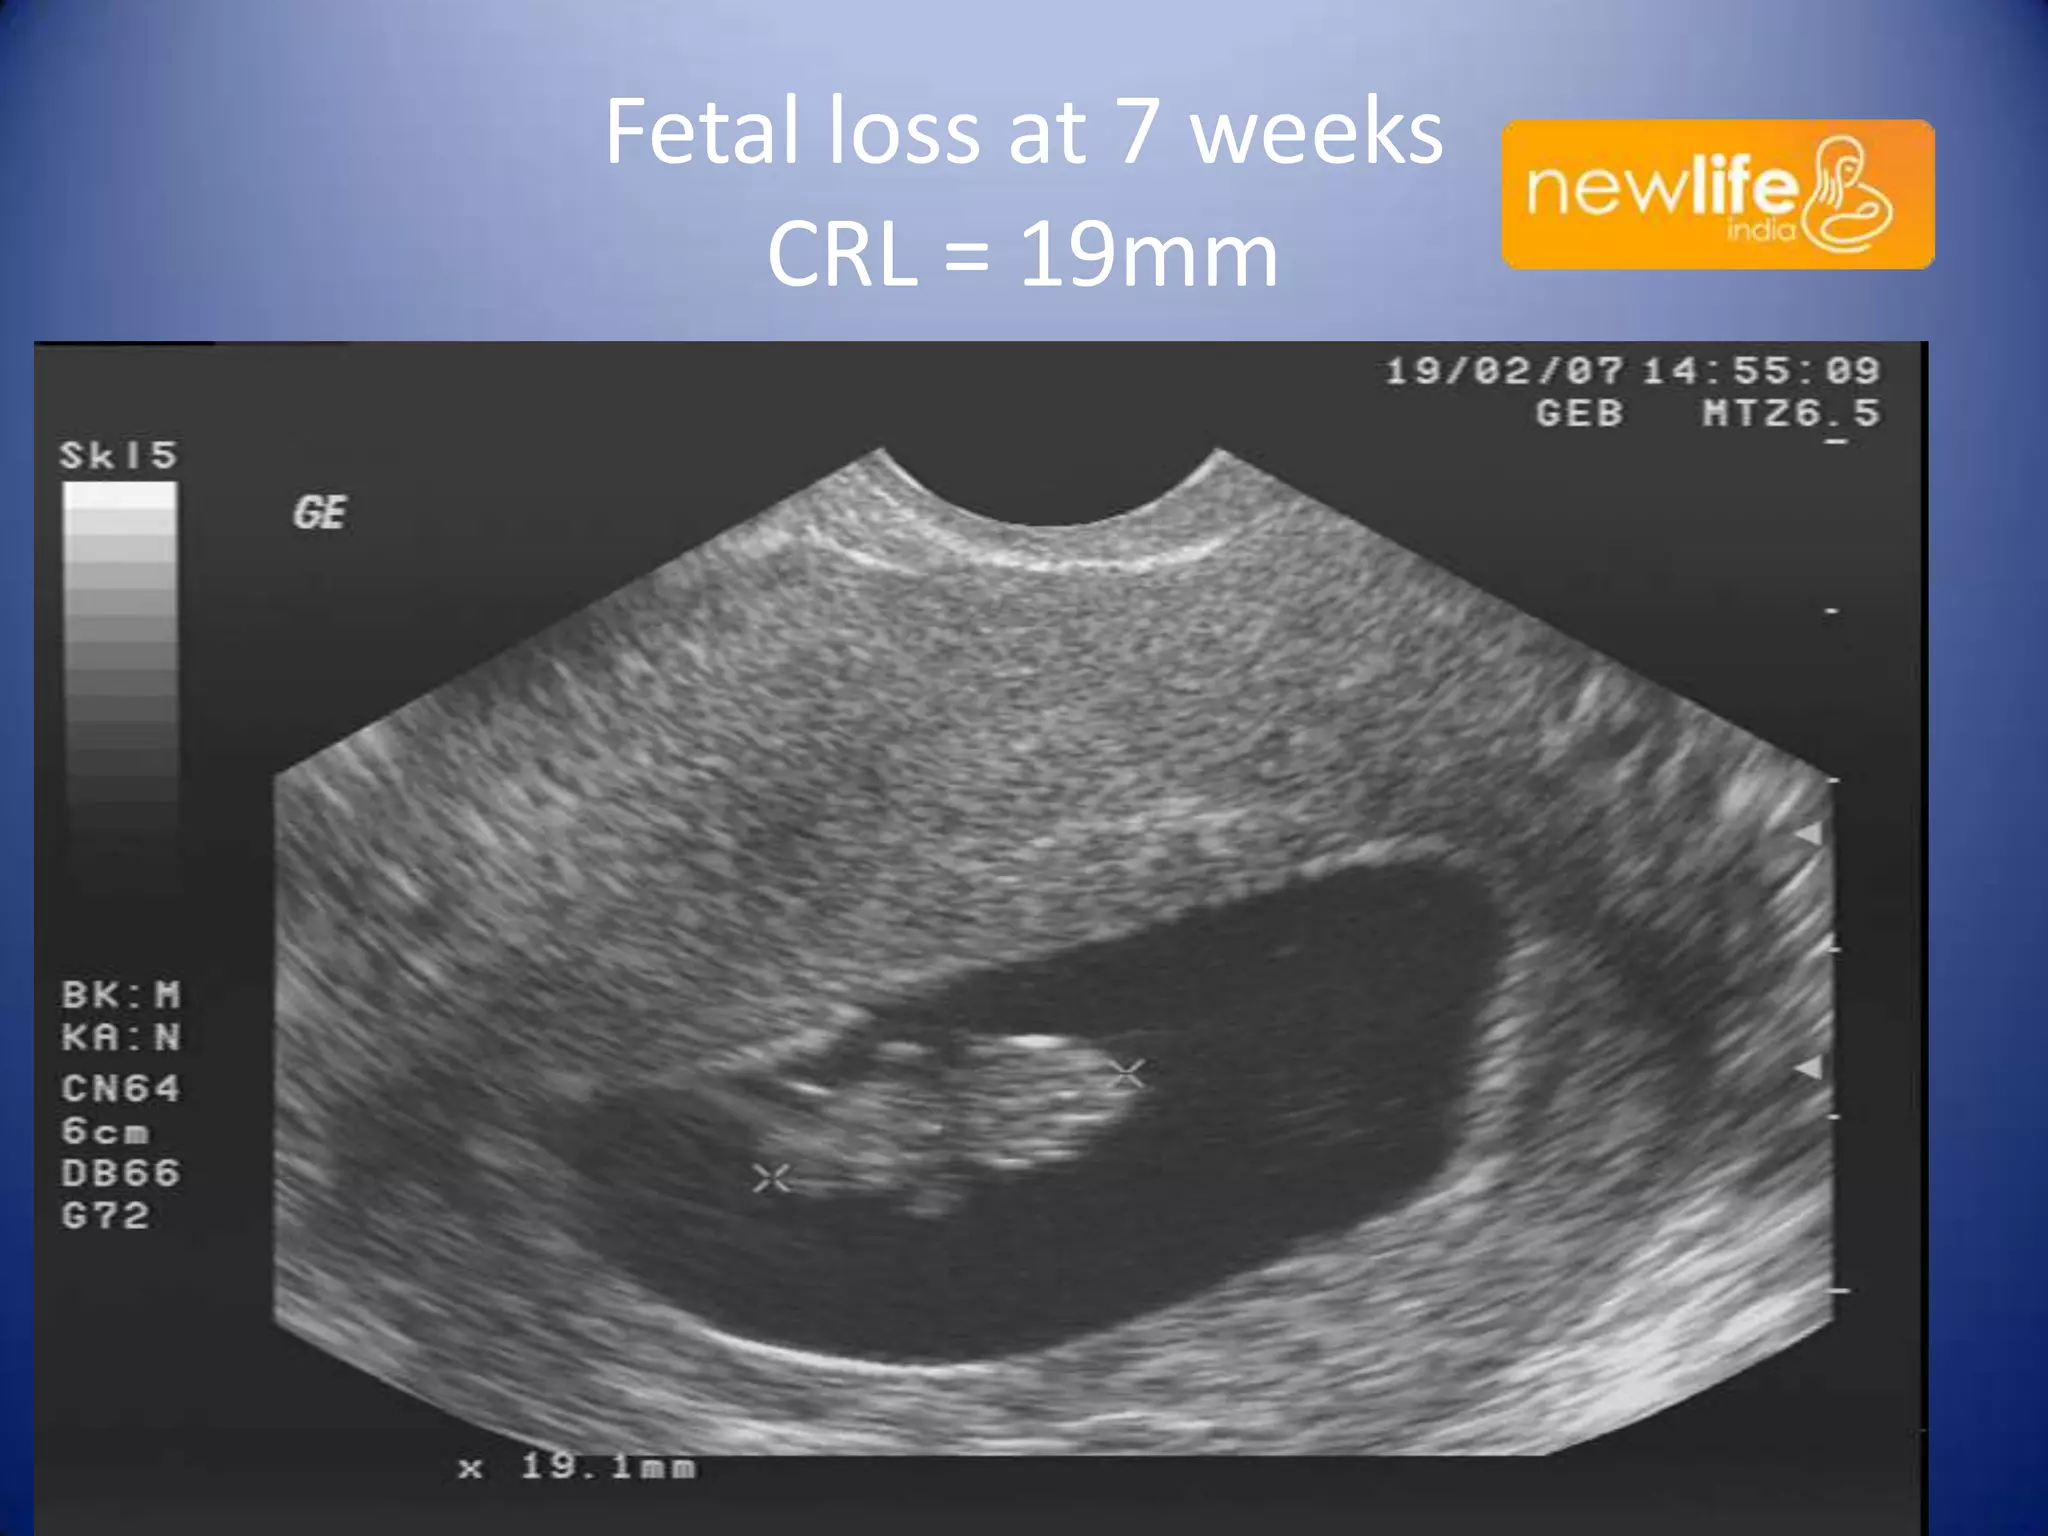

Fetal loss at 7 weeks

CRL = 19mm

Cytogenetics = 47XY+15

Small head compared to CRL, dysplastic face, partial encephalocele

Fetal loss at7 weeks CRL = 19mm 36

Cytogenetics = 47XY+15 Smallhead compared to CRL, dysplastic face, partial encephalocele 37